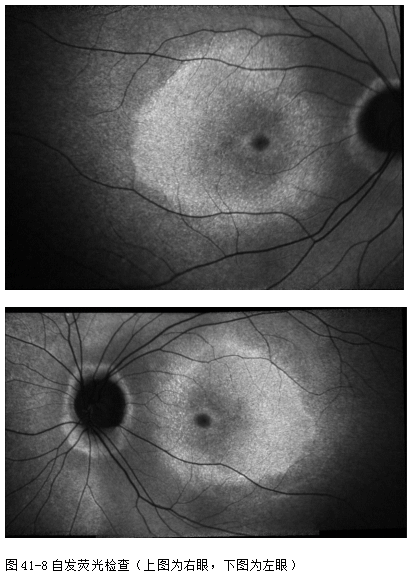

OCT(图41-7): 黄斑中心凹旁椭圆体带缺失。

自发荧光(图41-8):黄斑中心凹旁低荧光, 向外呈现以中心凹为中心的高荧光环,环外弥漫性低荧光。